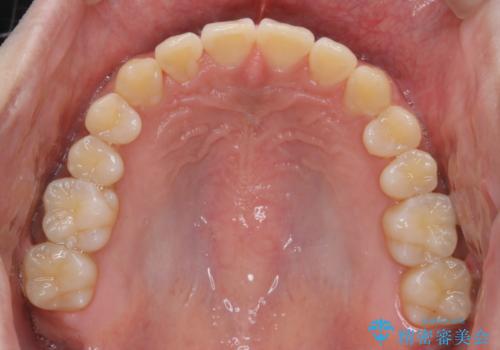

- 前歯のがたつきが気になるとご相談にいらした方です。左の奥歯の噛み合わせのズレも認められたため、インビザライン治療にて改善しました。

主訴である前歯のガタつきだけでなく、奥歯の噛み合わせからしっかり治療したため、治療期間が長めとなりました。患者様ご本人としては治療の途中で一時的にモチベーションが下がったこともあったようですが、最後まで頑張って続けて頂けたことで噛み合わせ及び見た目の改善を行うことが出来ました。